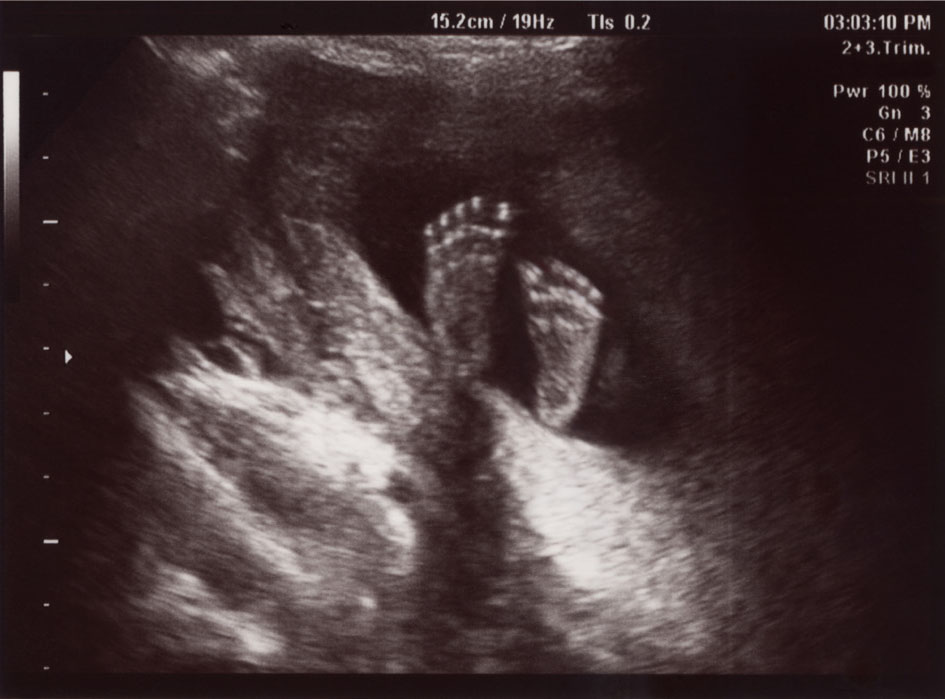

- LCCC offers 3-D/4-D technology and will attempt to obtain beautiful images for keepsakes. The quality of the images obtained will depend on the baby's position and cooperation.

- LCCC students will provide volunteers with printed paper images from the session.

- LCCC students will provide volunteers with a USB with images from the session.